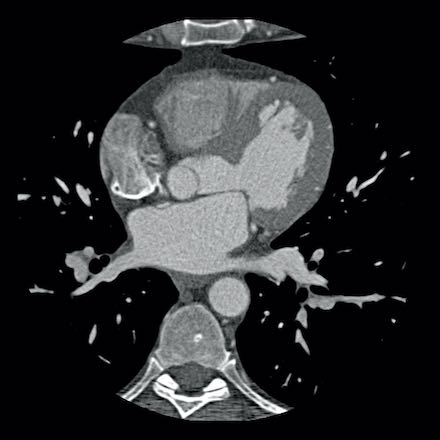

case 1 – CAD-RADS 2/P1

First, scroll through the scan.

Not all images are included. Some images without any abnormalities are skipped

from the series.

How would you describe the findings on the coronary CTA?

The findings are:

- Agatston score of

this patient was 14 (P1). Please, also note the calcification of the aortic valve. - Some partially

calcified and calcified plaques are present in the LAD with mild stenosis

(25-49%). - Calcified-plaque in

the LCX causing minimal stenosis (<25%). - Non-calcified

plaque in the distal RCA causing minimal stenosis (<25%). - This patient classifies

as CAD-RADS 2/P1, which means no further workup is needed.